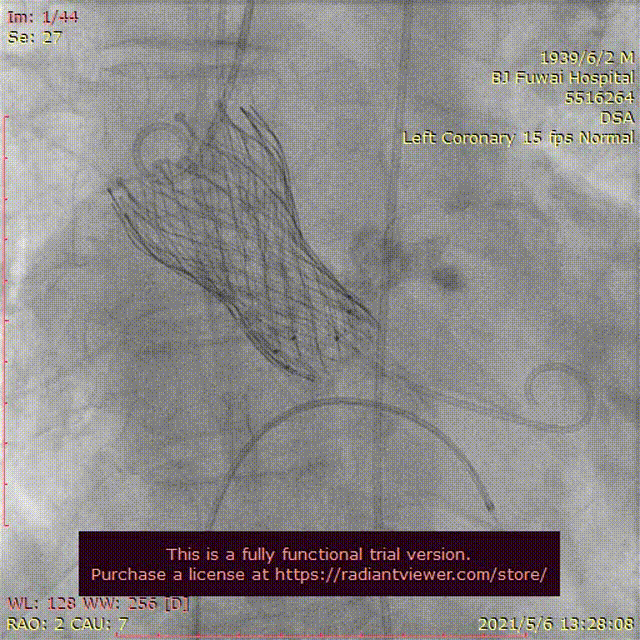

手术当天,病房护士提前行左肘正中静脉留置针作为补充液体通路;患者送达介入导管室后,省去经颈内静脉穿刺行中心静脉置管、经食道超声检查、术前导尿和麻醉师全身麻醉及气管插管或喉罩通气等过程;患者经过消毒及铺单后。半支(50mg)利多卡因局部麻醉后,穿刺右桡动脉作为辅入路,立即检测动脉血压;四支(400mg)利多卡因局部麻醉后,血管超声引导精准穿刺右股总动脉,两把ProGlide预埋处理后,作为主入路,置入20F 长导引鞘管(戈尔公司),立即动脉给予肝素5000单位;经右股静脉入路,将漂浮电极送入右心室心尖,临时起搏器调整至120次/分调试及测试患者的耐受性。主入路和静脉起搏器入路建立过程中,密切关注患者的血压心率等生命体征无明显异常,患者无明显不适。经右桡动脉送角度猪尾于右冠窦,采用右窦中心投照体位(右2°,足8°)行主动脉根部造影;

交换为头端塑形好的Landerquist超硬导丝,采用23 mm NUMED-II球囊对狭窄钙化的主动脉瓣进行预扩张,同时造影显示球囊完全封闭主动脉瓣,几乎无反流;

根据瓣上结构测量及球囊预扩张效果,采取“Down-size”策略,选择A-26 Venus A瓣膜,通过输送系统完成过弓和跨瓣;Venus A瓣膜精准定位于瓣环水平,

在临时起搏器控制心室快速起搏下完成瓣膜释放;

由于本例患者原瓣叶融合钙化较重,采用“瓣中瓣”技术植入另外一个A-26 Venus A瓣膜,

采用23mm NUMED-II球囊对植入的瓣膜进行后扩张;

最后造影显示新植入的瓣膜位置理想,少量瓣周反流,

跨瓣压差由术前30 mmHg下降至4 mmHg;即刻经胸超声评估主动脉瓣位植入生物瓣峰值流速为2.0 m/s,平均跨瓣压差为16 mmHg,少中量瓣周反流,左室射血分数为45%;评估患者心率为67次/分并且心电图较术前无明显异常,故即刻拔出临时起搏导线。整个手术过程仅采用局部麻醉,无任何镇静剂使用,患者全程清醒,配合良好,在球囊扩张主动脉瓣及瓣膜释放过程的血压及心率等生命体征与既往全麻相比无明显异常,患者略感心慌及无力。(图3)。术后患者平卧24 小时即下床活动,进行康复训练;采用阿司匹林100 mg (QD)和氯吡格雷75 mg(QD)行双联抗血小板治疗,术后4天顺利出院。

图3患者经导管主动脉瓣置换术及围术期操作

A:主动脉根部造影;B:23 mm球囊预扩张;C:26型号VenusA瓣膜植入;D:26型号VenusA“瓣中瓣”位置良好,少量瓣周漏;E和F:术前及术后经导管跨瓣压差;G:肘正中静脉留置针;H:患者全程清醒状态。